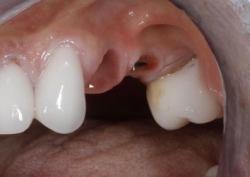

Примеры работ синус-лифтинга

Ежедневно мы восстанавливаем улыбку и уверенность в себе 5–7 пациентам.